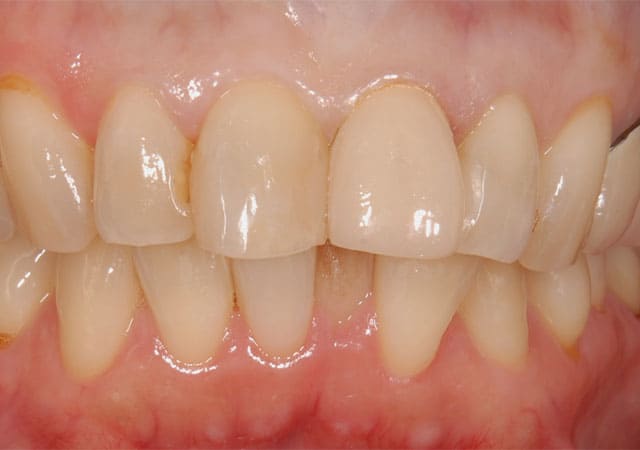

左上の前歯の見た目が気になることを主訴に来院されました。

虫歯を除去後、神経が露出しないように丁寧に削合しました。

仮歯に置き換え、見た目の確認をしてもらいました。

反対側に近い形となっており、元々の歯よりも大きいため、全体的に小さくしてほしいとの希望でした。